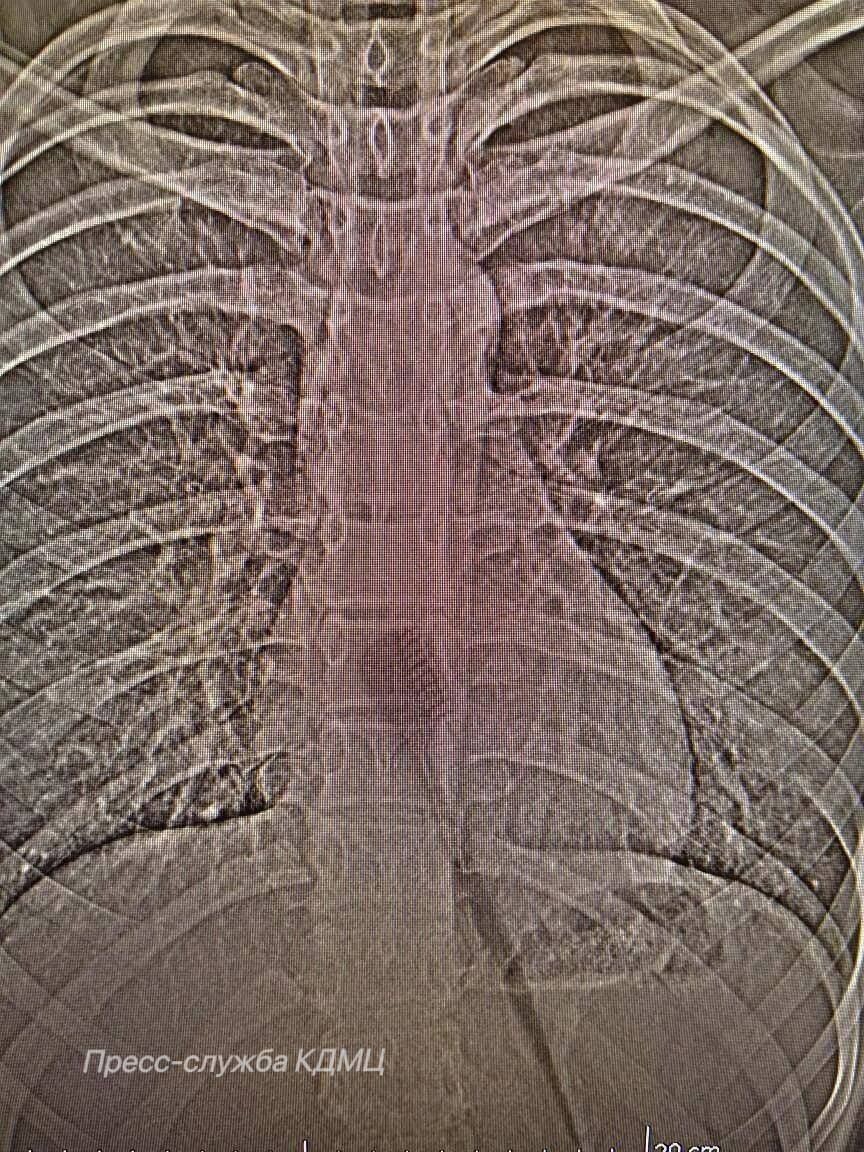

В КДМЦ Набережных Челнов поступила 13-летняя пациентка, которая случайно проглотила зубную щетку длиной 19 см. Как сообщает горздрав, щетка находилась в желудке и частично в пищеводе, создавая риск повреждения этих органов. Врач-хирург КДМЦ Дамир Хузин говорит, что механизм проглатывания в данном случае является стечением обстоятельств.

«Предположительно, произошла неожиданная реакция, возможно, резкий вдох или смех во время чистки зубов. Это могло спровоцировать непроизвольное сокращение мышц глотки, которое подтолкнуло щетку дальше по пищеводу. Так как анатомически пищевод имеет определенную эластичность, щетка, несмотря на свои размеры, смогла продвинуться вплоть до желудка», - объясняет врач.

Девочке провели эндоскопическую операцию – малоинвазивный метод, позволяющий извлечь инородное тело без полостного вмешательства. Это позволило аккуратно удалить предмет через естественные пути, минимизируя риск осложнений и ускоряя процесс восстановления пациентки. Подросток прошла период реабилитации, была выписана из КДМЦ и вернулась к обычной жизни. Случаи проглатывания инородных тел детьми – явление частое, но проглатывание предмета такого размера, конечно, редкость.